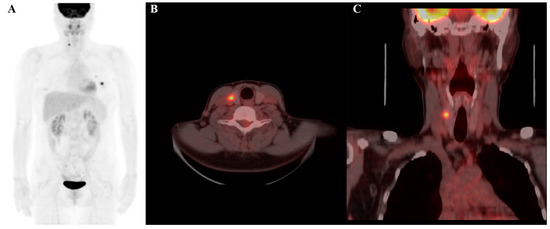

The listed radiomics features are valuable for cancer diagnosis as they capture specific tumor texture and intensity patterns associated with malignancy. These features help assess tumor heterogeneity, an indicator of aggressive behavior. In particular, the large-dependence low-gray-level emphasis (LDLGLE) in the gray level-dependence matrix (GLDM) feature is related to areas where low-intensity signals (often seen in less metabolically active regions) depend on surrounding pixel values, which can be indicative of the structural characteristics of a tumor [36]. Benign tumors are often more homogeneous and may have lower gray-level textures, which might increase the value of features like LDLGLE, whereas malignant tumors are generally more heterogeneous, with more irregular and higher intensity patterns, potentially leading to lower values for this feature. Features such as LDLGLE are indicative of tumor heterogeneity, reflecting areas where low-intensity signals depend on surrounding pixel values. In the context of thyroid nodules, this feature may correspond to regions with less metabolically active tissue that are structurally heterogeneous—an attribute often associated with malignant lesions. These characteristics align with the known biological behavior of thyroid cancers, which typically exhibit greater textural and metabolic irregularity compared to benign nodules. Thus, this feature provides insight into tumor composition and behavior (Figure 4 and Figure 5).

Figure 4.

F-18 FDG PET/CT image of a 69-year-old female patient, highlighting a thyroid incidentaloma in the right lobe of the thyroid gland: (A) maximum intensity projection (MIP); (B) axial PET/CT image; and (C) coronal PET/CT image. The lesion demonstrates increased FDG uptake with a maximum standardized uptake value (SUVmax) of 9.2. Radiomic features include a log-sigma-2-0-mm-3D_glszm_SmallAreaEmphasis value of 0.553 (relatively low) and a wavelet-HLH_gldm_LargeDependenceLowGrayLevelEmphasis value of 33.814 (relatively high). Despite the high SUVmax, the final diagnosis confirmed the nodule to be benign.